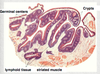

What is a lymphoid nodule? Describe its formation.

- Transient area of lymphocyte differentiation found in peripheral tissues (mucosa)

- Formation

- primary lymphoid nodule (follicle)

- secondary nodule

- mantle

- germinal center: B cell proliferation

Describe a Peyer’s Patch.

- lymphoid nodules found in intestine

- developed lymphocytes can interact with specialized M cell on epithelial wall to have antigen presented

- **also found in mucosa of appendix